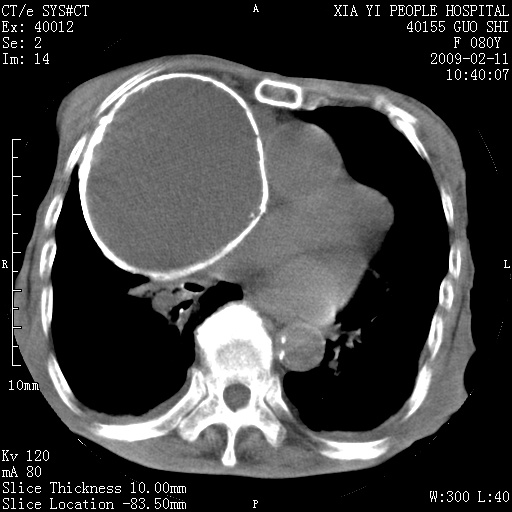

以下是引用随光逐影在2009-2-16 16:34:00的发言:[br]1)考虑右前纵隔皮样囊肿。2)双侧少量胸腔积液。

以下是引用zjzjr在2009-2-16 17:30:00的发言:[br]支持囊性畸胎瘤 双侧少量胸腔积液。